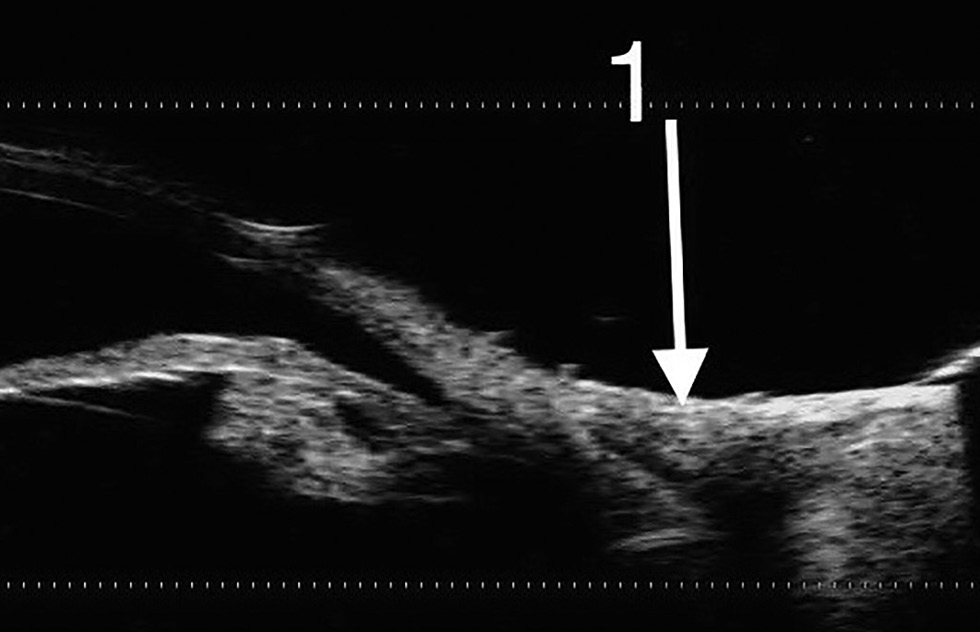

При динамическом наблюдении особенно тщательно следили за состоянием роговицы, пересаженных лоскутов конъюнктивы и обнажённого участка склеры. В раннем послеоперационном периоде клинически у всех животных отмечали отёк и гиперемию тканей конъюнктивы. Признаков токсикоаллергической реакции не наблюдали ни в одном из случаев. В зоне дефекта определяли плотную белесоватую ткань с бугристой поверхностью. По данным УБМ на 7-е сутки после операции в области аппликации клея и фиксации конъюнктивальных лоскутов визуализировали гиперэхогенную линейную пресклеральную структуру — это слой клеевой плёнки. Кроме того, выявляли локальное утолщение конъюнктивы со снижением эхогенности в зоне вмешательства (рис. 1). По данным ОКТ были получены изображения интактной роговицы и неравномерно утолщённой конъюнктивы в зоне хирургического вмешательства (рис. 2).

Рис. 1. Ультразвуковая биомикроскопия на 7-е сутки после операции. В проекции конъюнктивы гиперэхогенное линейное включение — слой клеевой плёнки, незначительное утолщение и снижение конъюнктивы (стрелка).

Fig. 1. Ultrasound biomicroscopy on Day 7 post-surgery. In the projection of the conjunctiva, a hyperechoic linear inclusion is visualized: a layer of adhesive film, with a slight thickening and reduction of the conjunctiva (arrow).

Через 45 суток после операции при биомикроскопии области дефекта визуализировали конъюнктиву, не отличающуюся от прилежащих тканей по цвету и плотности. Уменьшение глубины верхнего и верхнего внутреннего сводов по сравнению с дооперационными данными не отмечалось. Эхографическая оценка состояния конъюнктивы не выявила различий между акустической плотностью интактных тканей и тканей в области пересаженных лоскутов. В области дефекта определяли нормальную конъюнктиву средней эхогенности толщиной от 0,1 до 0,3 мм (рис. 5).

Рис. 5. Ультразвуковая биомикроскопия на 45-е сутки после операции. Стрелкой обозначена зона хирургического вмешательства (1).

Fig. 5. Ultrasound biomicroscopy on Day 45 post-surgery. The arrow marks the surgery area (1).